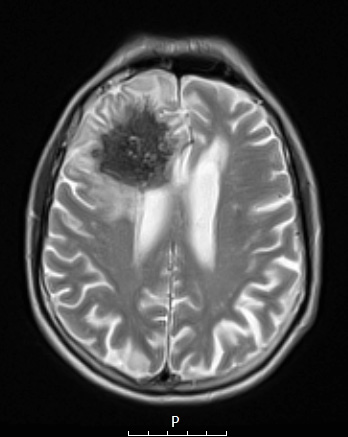

7A5 Amyloidoma (Case 7) T2 noC - Copy

The lesion is hypointense on this T2-weighted scan without contrast.